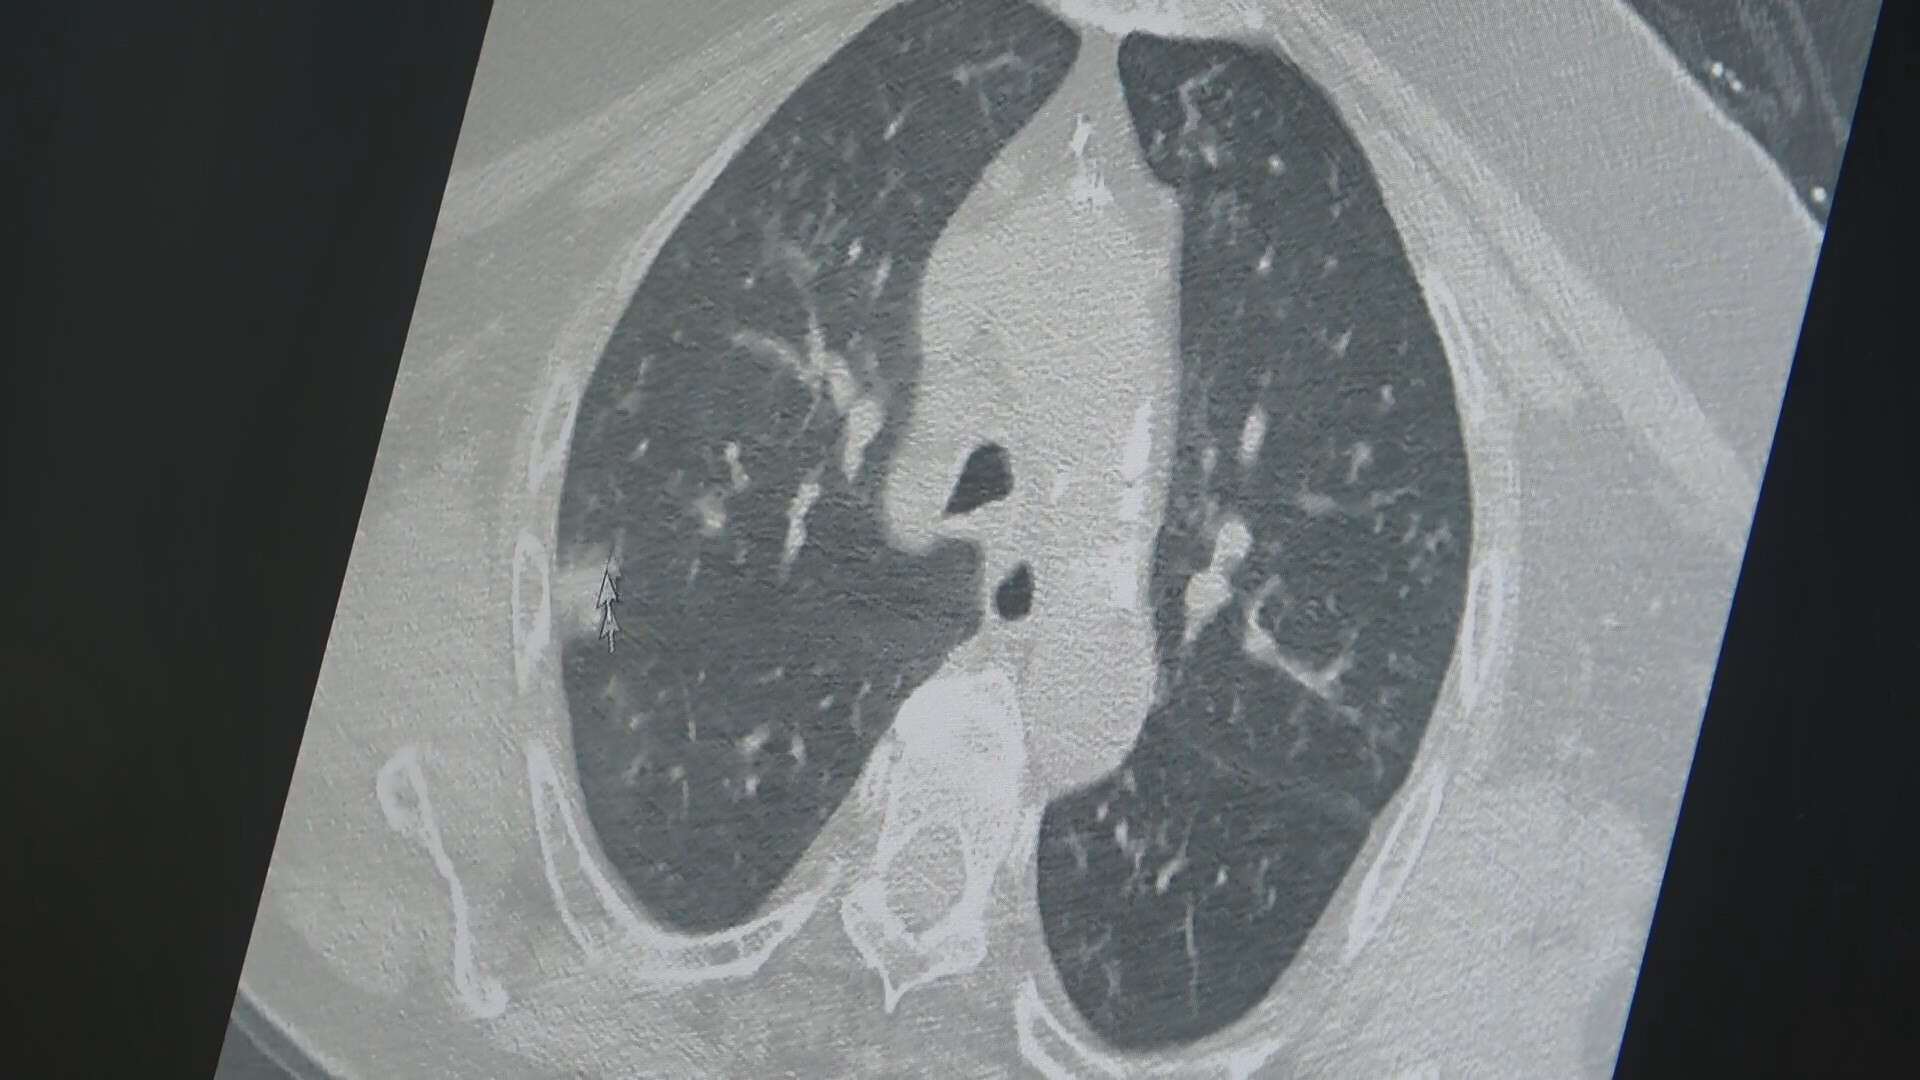

“Asrın felaketi” olarak nitelendiren deprem sonrasında ortaya çıkabilecek bulaşıcı hastalıklar ve zatürre ile ilgili uyarılarda bulunan Göğüs Hastalıkları Uzm. Prof. Dr. Şevket Özkaya, binlerce vatandaşın kış mevsiminde dışarda kaldığını belirterek depremzedelerde solunum yolu enfeksiyonları çok fazla olduğunu ifade etti.

Depremden kurtulanların büyük bir kısmı soğukta, açık havada yaşamak zorunda kaldı. Bir kısmı da toplu yerlerde yaşamaya başladı. Özellikle depremden kurtulan vatandaşlarımız da bu soğuk havanın etkisiyle, geceyi soğukta geçirmeleri nedeniyle bronşit dediğimiz solunum yolu enfeksiyonları çok fazla var. Çok fazla ateşi olan çocuklarımız var. Öksürük ve ateşle seyreden depremzedelerimiz geliyor. Vatandaşlarımızın yarısı açık havada soğukta yaşıyorlar. Yarısı da toplu yerlerde yaşıyor. Toplu yerlerde yaşayanlarda ise viral enfeksiyonlar sık olarak görülebilir. Şikayeti olan depremzedelerin en kısa zaman doktorlara gitmesini öneriyoruz. Bundan sonra daha büyük felaketler bizi beklemesin ve bir an önce yaralarımızı sarmaya başlayalım” diye konuştu.